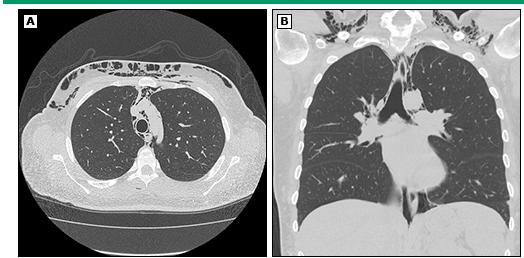

皮肌炎和多发性肌炎患者的肺部并发症很常见,也是炎症肌病患者的重要死因之一。常见的临床表现为呼吸困难、咳嗽。采用敏感性高的高分辨率CT、肺功能检查可在70%的患者发现肺部病变。

除呼吸肌无力外,肺部组织炎症也是重要原因。炎性肌病损伤肺部组织时表现为间质性肺疾病(interstitial lung disease, ILD)。根据肺部受累的病理可以分为:

患者的间质性肺疾病的出现时机不定。可以在皮疹、肌肉症状出现前,也可以同时或此后出现。少数人存在快速进展的肺部病变,例如急性间质性肺炎带来弥漫性肺泡损伤。但大多数患者表现轻微、进展缓慢。

每个拟诊皮肌炎或多发性肌炎的患者都应行高分辨率CT检查肺部。尽管肺间质病变患者可在吸气后期听到固定的音调偏高水泡音----velcro啰音。但并非所有肺间质病变都存在。单纯以肺部听诊正常就排除掉肺间质病变是错误的。

皮肌炎的胸部CT表现

自发性纵隔积气是炎性肌病一种罕见但严重的并发症。皮肌炎更常见该并发症,尤其是「无肌病性皮肌炎」。有研究显示,约50%的自发性纵膈积气发生在「无肌病性皮肌炎」病人身上。纵隔积气的典型表现是急性发作的胸骨后胸痛伴皮下气肿。这时可以观察到颈部和面部肿胀。医生按压皮肤时有明显的「握雪感」,甚至可以听到沙沙的气体被挤压声音。

自发性纵膈积气